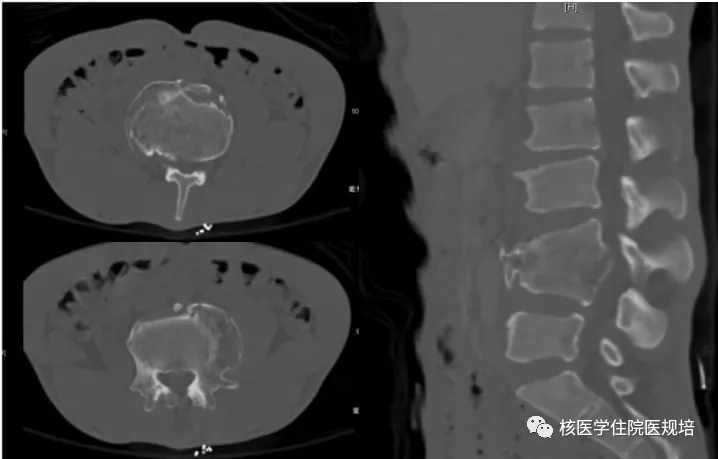

患者男性,30岁, 3个月前无明显诱因突发大小便失禁,同时伴下肢活动障碍,为进一步诊治就诊于我院。既往史:出生后诊断为先天性无痛无汗症,其他无特殊病史。查体:患者轮椅进入病房,神志清楚,对答切题;全身皮肤干燥、见多处瘢痕,皮肤痛觉缺失,指甲发育不良,脊柱生理屈度存在,无明显棘突压痛。双上肢未见明显畸形,肌力、肌张力未见明显异常。左下肢可见膝关节不规则隆起,表面不光滑,质硬,无波动感,关节屈伸正常,局部皮温正常,无皮肤红肿、破溃或静脉怒张,压痛(-);右下肢未见明显异常。双下肢感觉较弱,巴氏征(-)。实验室检查无明显异常发现。腰椎X光片及CT(图1.2)检查发现腰椎退行性变,L3、L4椎体融合,骨小梁结构模糊,L5/S1椎间盘膨出,前纵韧带钙化;多关节部位X光片示右髋关节(图3)髋臼扩大、骨质吸收,股骨头脱位,骨骺未融合,残端如刀削状,关节肿胀,内见多发碎骨片;左膝关节(图4)正常关节结构消失,关节对位差,骨端膨大,周围见多发游离骨块,股骨下段、胫骨平台见骨质破坏,关节周围软组织肿胀;右踝关节(图5)诸骨在位,胫腓骨远端膨大变形,距骨变扁,诸骨骨质密度弥漫减低,骨小梁稀疏,内外踝边缘可见骨质增生;关节间隙狭窄。为进一步了解全身骨病变情况行99mTc-MDP全身骨显像(图6)。

图2.

图3.